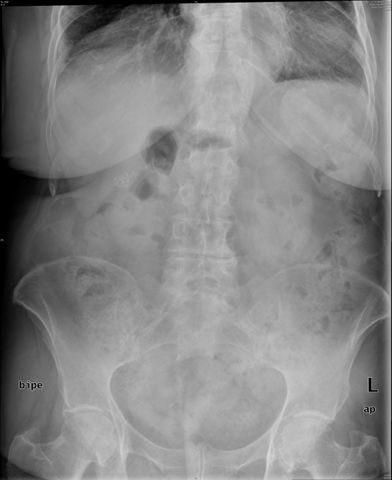

Diverticulosis de colon.

Diverticulosis de colon. Megacolon.

Dolico-megacolon.